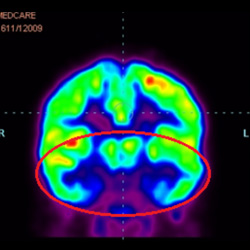

這證明細(xì)胞療法是治療腦癱兒童安全有效的方法。細(xì)胞療法可以更新大腦損傷的核心,并且可以通過 PET CT 掃描來監(jiān)測大腦的改善情況。這些細(xì)胞療法與標(biāo)準(zhǔn)治療一起促進(jìn)腦癱兒童的生長和改善。